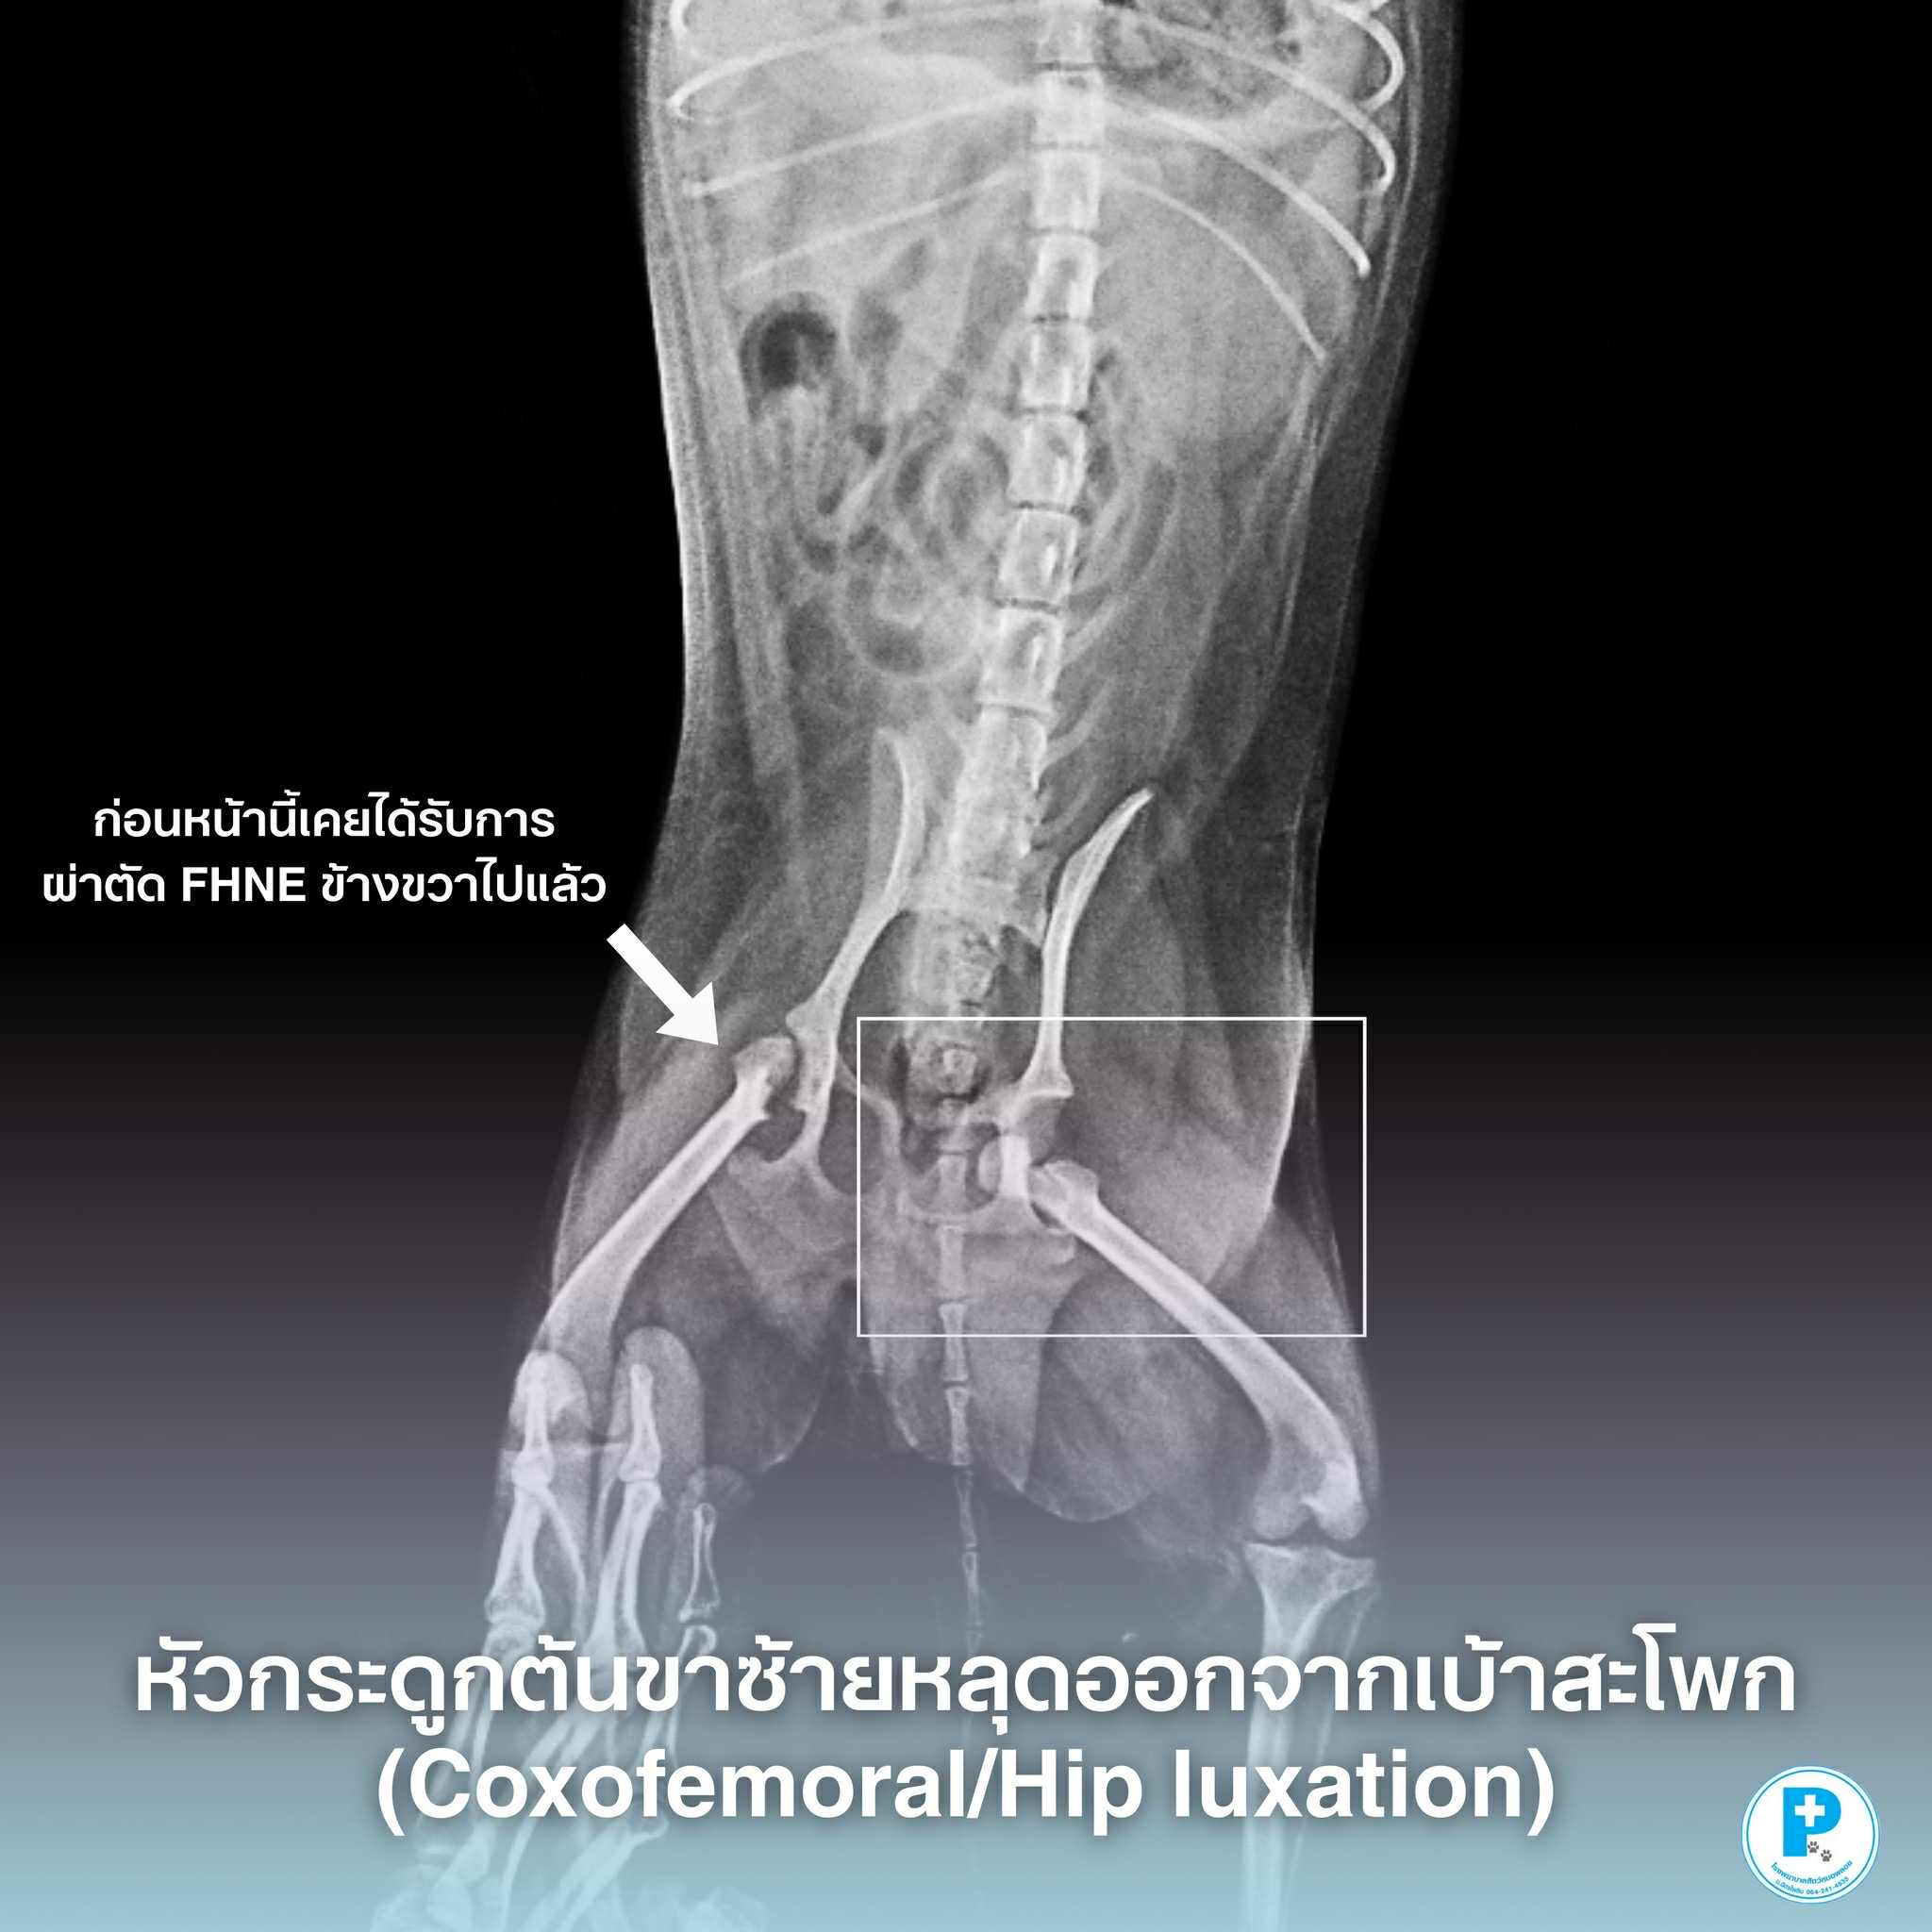

เคสนี้น้องหมาชื่อลูก้ามาด้วยอาการ ยกขาซ้าย เดินกะเผลก และแสดงอาการเจ็บขา ตรวจสอบประวัติพบว่า เคยผ่าตัดตัดหัวและคอกระดูกต้นขาด้านขวา (FHNE) มาก่อน

เมื่อตรวจเอกซเรย์ พบว่า

ข้อสะโพกด้านซ้ายเคลื่อน

(Coxofemoral luxation – Left)

คือภาวะที่ หัวกระดูกต้นขาหลุดออกจากเบ้าสะโพก